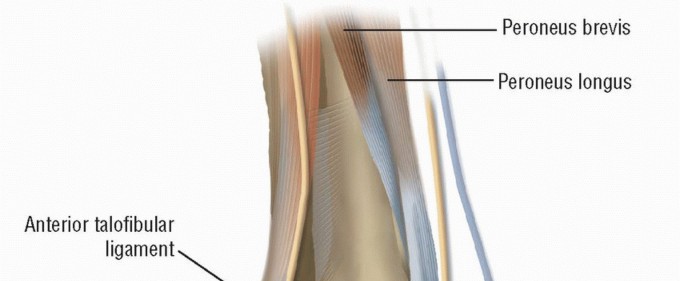

DEFINITION Ankle sprains are the most common athletic-associated injury: They represent up to 40% of all spor…